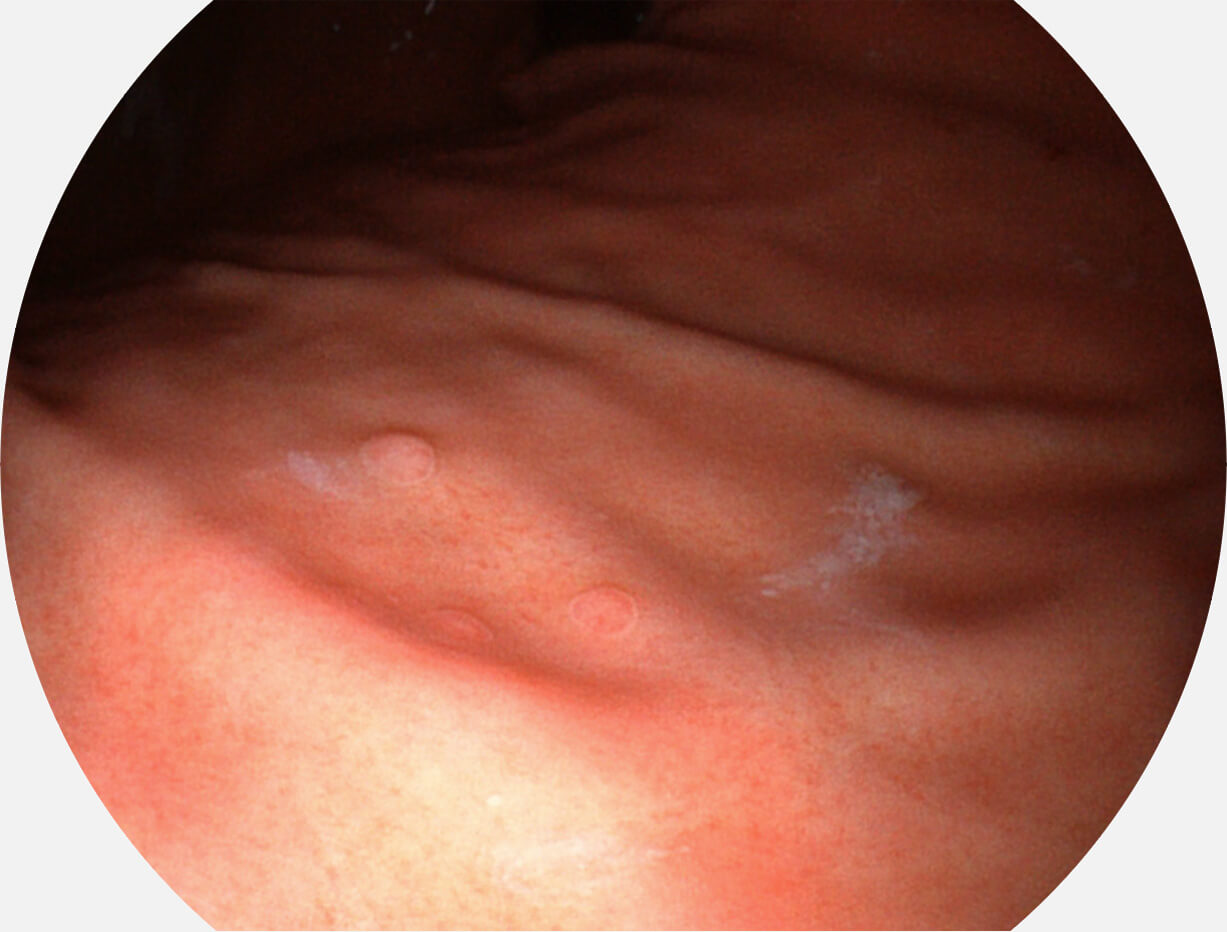

Spectral Focused lmaging, SFI

图像具有高亮度、高黏膜血管颜色对比度的特点,且不改变粘液、食物残渣、粪便的基本颜色,可在中远景下进行观察,助力消化道早期疾病的诊断。

SFI图像

Versatile Intelligent Staining Technology, VIST

强调浅层黏膜结构的同时,保证照明亮度和提升浅层微血管与中层血管颜色对比度,病变边界更清晰。